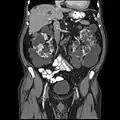

Abdominal CT scan of an adult with autosomal dominant polycystic kidney disease: Extensive cyst formation is seen over both kidneys, with a few cysts in the liver, as well. (Coronal plane)